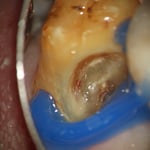

メタルインレー下にはレジンの覆髄が施されていましたが、接着しておらず、ポロリと取れました。これが、2次齲蝕(治療後の虫歯の再発)の原因です。多量の軟化象牙質(虫歯)を除去していくと、歯髄腔(神経と血管が入っている部屋)まで紙一枚。うっすら赤い血流も確認できます。齲蝕除去中に口蓋側の咬頭が破折しましたので、グラスファイバーポストによって、生活歯の支台築造。神経も取らずに残せる歯は、本当に多くあります。